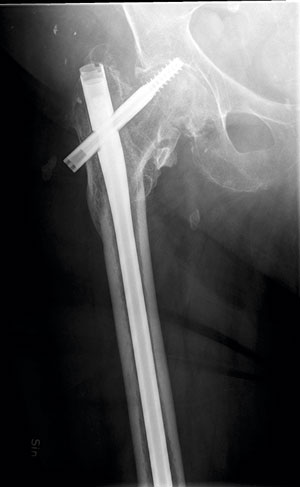

Haveri av osteosyntesmaterial. Till vänster: Patient med en initialt odislokerad cervikal höftfraktur. Patienten besvärades sedan operationen av värk i ljumsken och lateralt kring höften. Värken blev så pass uttalad att den störde nattsömnen. På slätröntgen sågs icke-läkning i frakturen, och den kaudala skruven hade backat och stack ut i mjukdelarna. Till höger: Patient med subtrokantär femurfraktur som opererats med lång märgspik. Patienten hade smärta och stelhet i höften och värk i framför allt ljumsken. Initialt var patienten nöjd med sin höft men hade fått mer och mer ont de senaste månaderna och hade svårt att promenera till närmaste affären. Osteosyntesmaterialet hade migrerat kraniellt, och kollumskruven hade skurit ut genom caput och penetrerade leden.